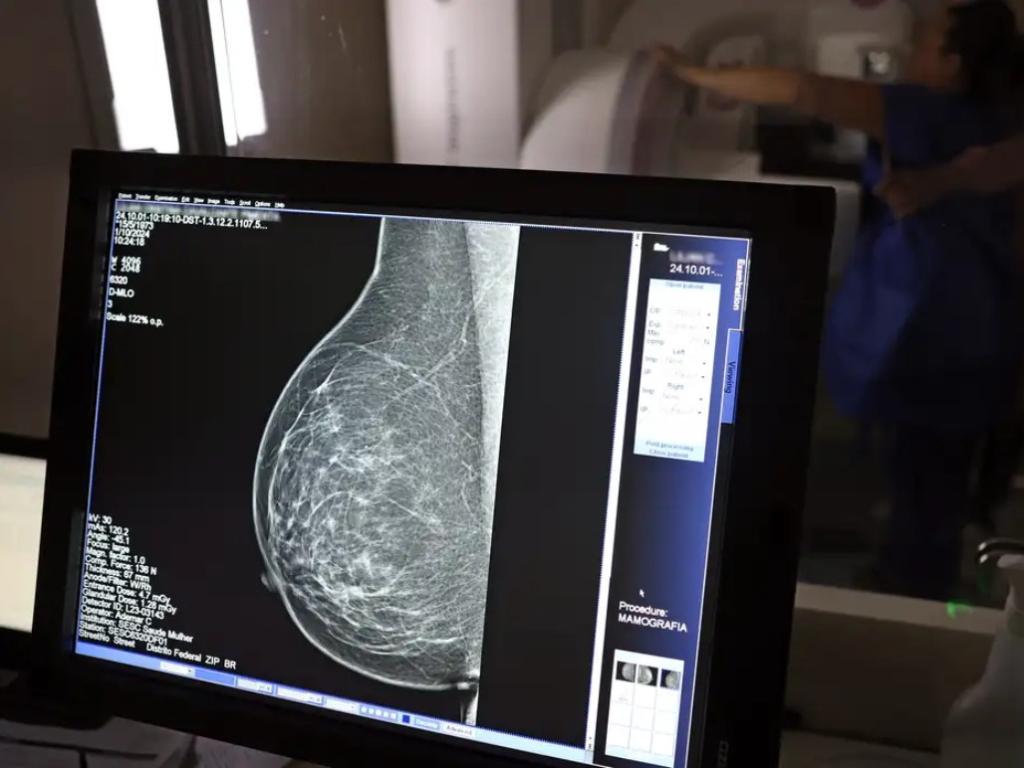

Uma nova lei, publicada nesta segunda-feira (6), reforça o direito do trabalhador com contrato via Consolidação das Leis do Trabalho (CLT) de se afastar até três dias por ano para realizar exames preventivos de câncer, em desconto salarial.

O direito já estava incluído na CLT desde 2018. A partir de agora, as empresas passam a ser obrigadas a divulgar essa informação, além de outras relacionadas a campanhas oficiais de vacinação contra o HPV e sobre o acesso a serviços de diagnósticos de cânceres de mama, próstata e de colo do útero.

O texto estende o uso das folgas também para a realização de exames preventivos do HPV, além dos de câncer que já estavam previstos na legislação anterior. A a Lei 15.377 foi sancionada pelo presidente Luiz Inácio Lula da Silva, e publicada na edição do Diário Oficial da União (DOU).